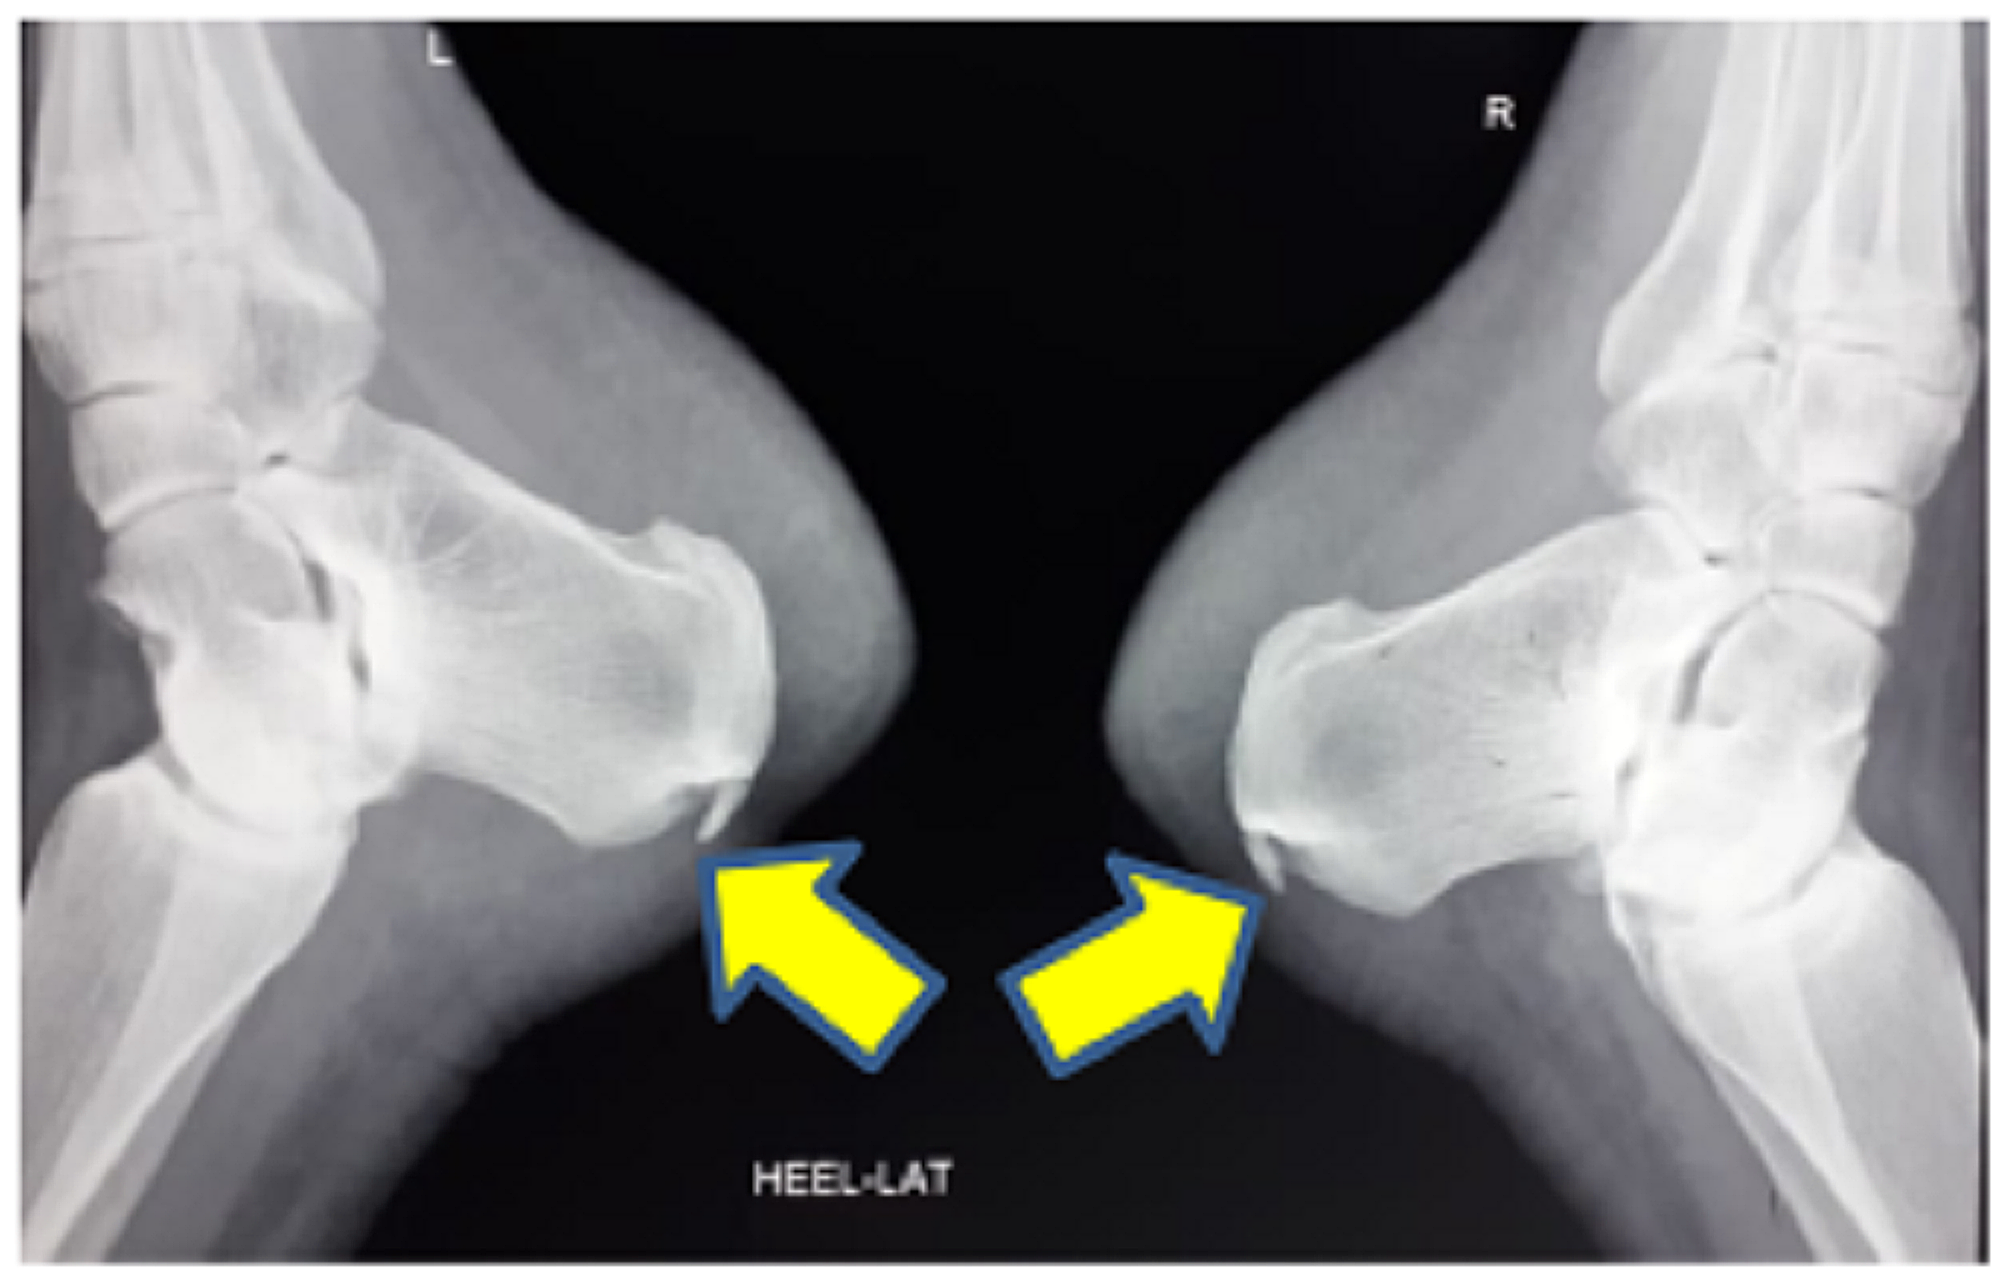

Pump Bump Swelling . The soft tissue near the achilles tendon becomes irritated when the bony enlargement rubs against shoes. Haglund deformity, also known as a pump bump, bauer bump, or mulholland deformity, is defined as bony enlargement formed at the. Additional tests, such as an mri. Haglund’s deformity is sometimes called a “pump bump” because it’s especially painful to wear shoes like pumps (high heels). Haglund’s deformity is a bony enlargement on the back of the heel. Haglunds deformity is an enlargement of part of the bone on the back of the heel. The diagnosis of a pump bump typically begins with a physical examination, where the podiatrist or another care provider looks for signs of pain, swelling, warmth and redness in the affected area. It irritates the soft tissues around the achilles tendon and. Changing footwear and doing stretching exercises may. Haglund’s deformity is a bony ridge or bump that appears on the back of the heel bone, where the achilles tendon attaches to the heel. Haglund’s deformity is a symptomatic osseous prominence of the posterolateral corner of the calcaneus resulting in posterior heel pain and.

Haglund’s deformity is a symptomatic osseous prominence of the posterolateral corner of the calcaneus resulting in posterior heel pain and. The diagnosis of a pump bump typically begins with a physical examination, where the podiatrist or another care provider looks for signs of pain, swelling, warmth and redness in the affected area. Haglund deformity, also known as a pump bump, bauer bump, or mulholland deformity, is defined as bony enlargement formed at the. Haglund’s deformity is sometimes called a “pump bump” because it’s especially painful to wear shoes like pumps (high heels). The soft tissue near the achilles tendon becomes irritated when the bony enlargement rubs against shoes. It irritates the soft tissues around the achilles tendon and. Haglunds deformity is an enlargement of part of the bone on the back of the heel. Haglund’s deformity is a bony enlargement on the back of the heel. Changing footwear and doing stretching exercises may. Haglund’s deformity is a bony ridge or bump that appears on the back of the heel bone, where the achilles tendon attaches to the heel.